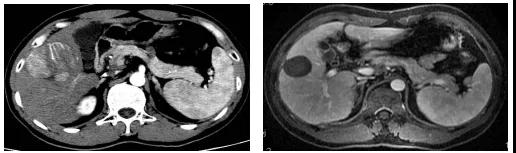

图3、该例大于15cm的巨大肝癌,经过2次DEB-TACE联合FOLFOX HAIC治疗,肿瘤明显缩小和肿瘤完全坏死。